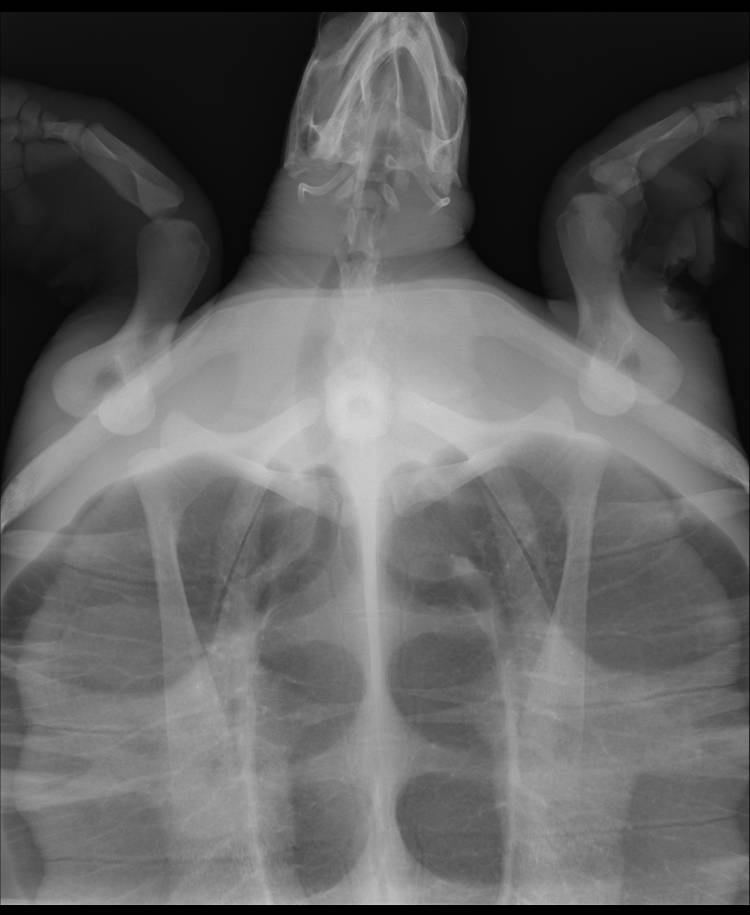

X-rays of the turtle's injured flipper revealed that despite the wound looking serious, there were no breaks (a good thing as this often requires the flipper to be amputated). We were able to clean the wound and will ensure that it is allowed to heal naturally. The turtle is currently on a course of antibiotics to cure any undetected infection.

Despite his external injuries, X-ray results were promising.